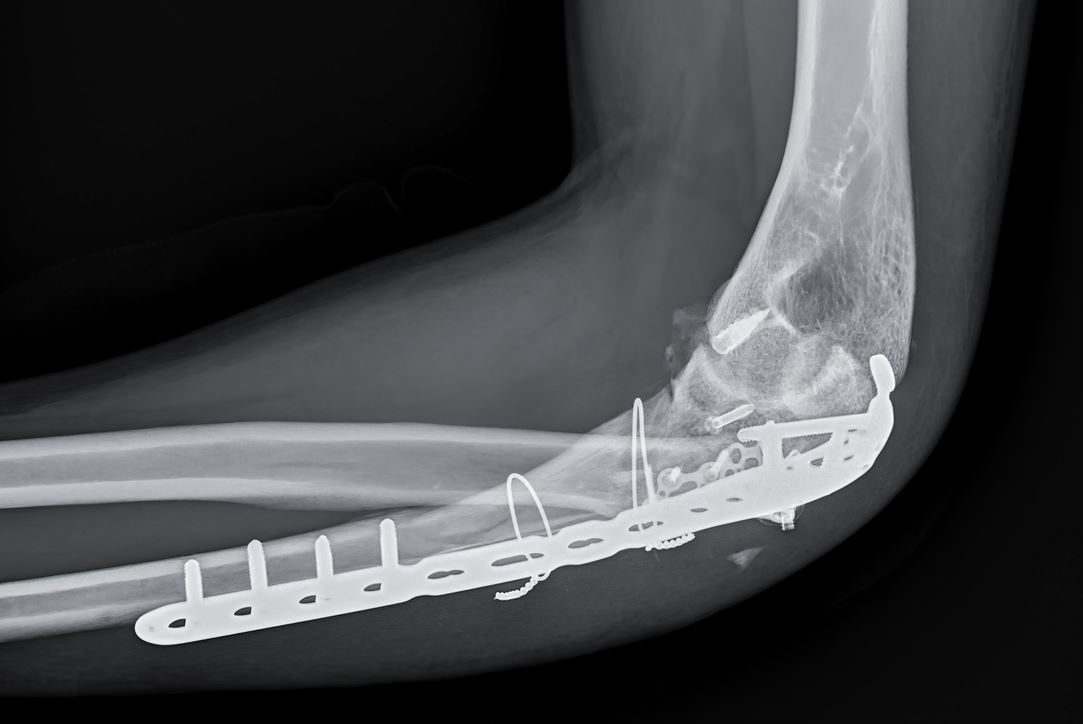

2- التثبيت الداخلي

يُدعى بالاستجدال، ويتمُّ تطبيقه أثناء العمل الجراحي، وخاصةً بعد الردّ المفتوح، وفي حالاتٍ خاصةٍ من الردّ المغلق، وتُستخدم فيه مواد عديدة منها:

2- البراغي: توضع حسب نوع العظم الذي توضع فيه (قشريّة أو إسفنجية)، وتكون بأقطارٍ مختلفة، ولها عدة تصنيفات (ناقصة، كاملة الحلزنة، مقناة)، وتستخدم في التثبيت المفتوح.

3- الصفائح: عديدة الأنواع (عادية، ضاغطة، تشريحية، مقفلة)، وتكون مصنوعةً من مادة الفولاذ غير قابلة للصدأ أو مادة التيتانيوم.

4- السفافيد: يتمُّ من خلالها تثبيت الكسر بسفودٍ مقفل داخل نقيّ العظم، وتستخدم بشكلٍ أكثر شيوعاً في كسور العظام الطويلة، مثل: كسور العضد، أو الفخذ، أو الساق.